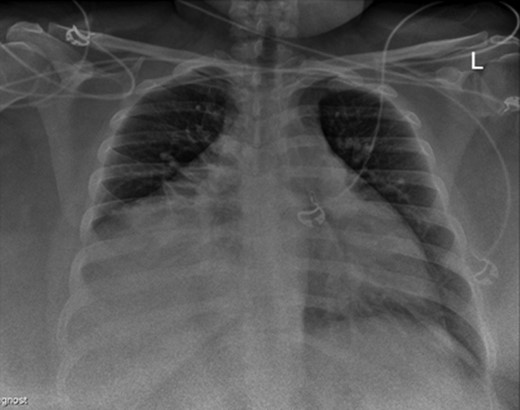

A 28-year-old asymptomatic obese female presented to the bariatric clinic for weight reduction surgery. During the routine bariatric preoperative evaluation, examination revealed decreased breath sounds bilaterally and dullness to percussion in the anterior chest. On X-ray, widening of the mediastinum with possible intrathoracic mass was identified and the patient was referred to thoracic surgery. Further laboratory investigation of common tumor markers, such as ABG, AFP, HCG, CA 19.9 and CEA, were all negative along with chemistry and hepatic panels. CT imaging was performed and revealed a large heterogeneous anterior mediastinal mass with fat and soft tissue. With possible differential including thymolipoma, liposarcoma and germ cell tumors, further imaging of the abdomen, brain and bones was performed and did not show any evidence of metastasis. CT-guided biopsy revealed a well-differentiated sclerosing variant liposarcoma with cellular-spindled areas. The cells were positive for CD34, desmin, S100 and MDM2. They were negative for SMA, CD117 and DOG1 (Figs 1–5).

Initial bariatric preoperative chest X-ray that led us to the diagnosis.